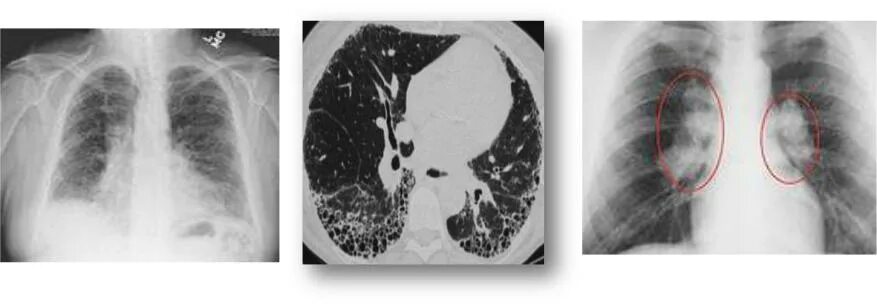

Линейный фиброз молочных